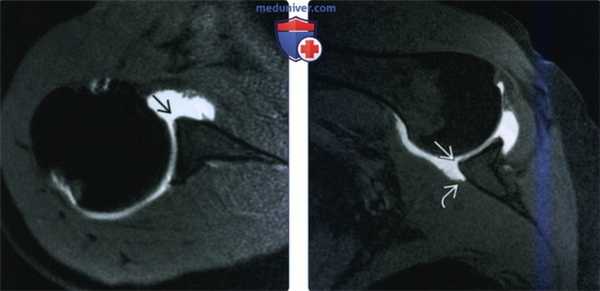

(Слева) На осевой МР-артрограмме Т1 FS пациента хронической передней нестабильностью и с недавним эпизодом вывиха видно, что отсутствует передняя губа с обнаженным суставным краем. Губа может смеситься или резорбироваться у пациентов с хроническими разрывами.

(Справа) На МР-артрограмме Т1 FS с отведением и наружной ротацией определяется хроническое повреждение Банкарта с обнаженным суставным краем. Передний пучок нижней суставно-плечевой связки не визуализируется, однако определяется отделение медиального края прикрепления передней капсулы к шейке лопатки.

(Слева) На осевой двойной контрастной КТ артрограмме кости при хроническом повреждении Банкарта видно, что передняя губа с обнаженным суставным краем отсутствует. Задняя губа в норме.

(Справа) На осевой MPT PDBИ FS застарелого повреждения Банкарта у пациента с передней нестабильностью определяется усиление сигнала В между передней губой В и сустав -ным краем. Разрывы Банкарта при отсутствии суставного выпота или свежего вывиха могут не определяться при стандартной МРТ.